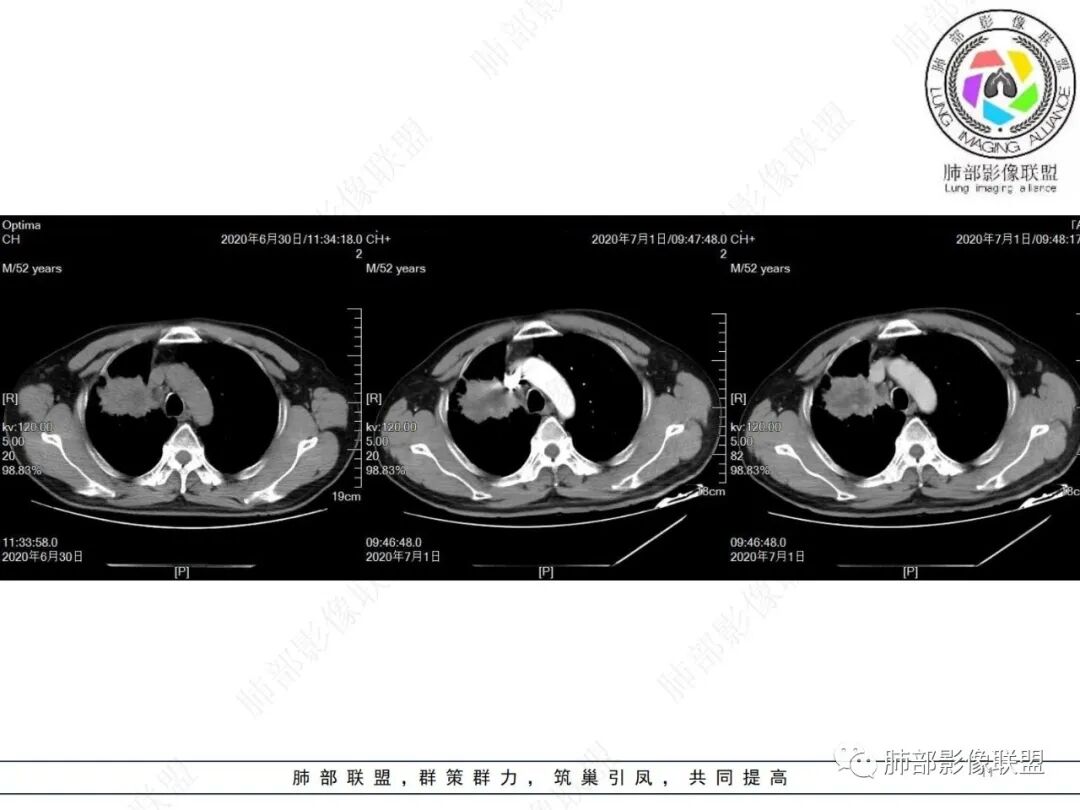

中年男性,有长期吸烟史,右肺上叶不规则肿块,边缘膨隆有分叶,支气管截断,不均匀强化,内有多灶性坏死,癌胚抗原升高,考虑肺癌可能性大,鳞癌可能。鉴别腺癌。

右肺上叶不规则形软组织密度肿块影,边缘见分叶,毛刺,病灶呈宽基底与胸膜相连,病灶内见坏死,增强扫描呈不均匀性强化,右肺上叶支气管截断,纵隔内见肿大淋巴结,肿瘤标志物增高,考虑鳞癌可能,鉴别小细胞癌,腺癌。

老年人,右肺上叶肺不张伴阻塞性炎症,右肺上叶支气管闭塞,增强病灶强化不均匀,可见边缘不清晰的坏死,纵膈淋巴结增大,考虑中央型肺癌,鳞癌可能性大。

右肺上叶不规则肿块,分叶、毛刺,上叶支气管截断,断端圆钝,不均匀强化,其内空泡及坏死,坏死边界不清,考虑腺癌或腺鳞癌,鉴别鳞癌

右肺上叶团块影,边缘膨隆,支气管近端截断,肿块内密度不均匀,见片状坏死,边界不清,纵隔肿大淋巴结,CEA明显增高,考虑恶性,鳞癌?腺鳞癌?

中年男性,长期吸烟,CT示右肺上叶肿块影,有分叶,毛刺,胸膜牵拉,支气管截断,边缘斑片影,病变内有坏死,强化,淋巴结肿大,首先考虑鳞癌可能性大,鉴别腺鳞癌

右肺上叶占位,支气管阻塞截断,病变周围可见结节及斑片状影,密度不均,坏死边缘不清,纵隔淋巴结肿大,中年男子,吸烟史,考虑鳞癌、腺鳞癌,鉴别结核

沼泽样坏死,支气管截断,周围阻塞性炎症,并淋巴道水肿,考虑腺鳞癌,鳞癌

右上叶支气管截断呈斜坡状,不均匀强化,低密度区实质区边界不清,老年男性,长期吸烟史,考虑恶性,鳞癌首选

长期抽烟的老头,右肺上叶不规则肿块,边缘膨隆有分叶,支气管截断,不均匀强化,内有片状坏死,考虑肺癌,常规思路鳞癌可能。鉴别腺癌。

中年男性,长期吸烟,右肺上叶不规则肿块,边缘膨隆有分叶,支气管截断,不均匀强化,内有多灶性坏死,癌胚抗原升高,考虑肺癌